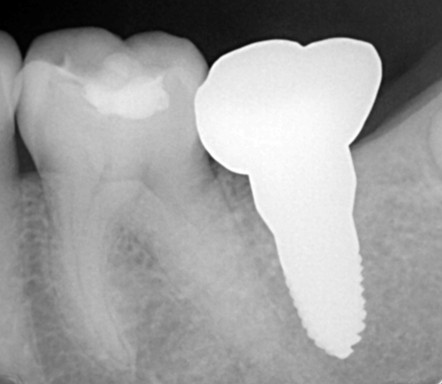

Prosthodontics (also known as dental prosthetics or prosthetic dentistry) is one of the nine dental specialties recognized by the American Dental Association (ADA). Prosthodontists specialize in the diagnosis, restoration, and replacement of missing teeth.

Extensive training and experience give prosthodontists a unique understanding of restoring the dynamics of a smile and healthy mouth with the creation of tooth prostheses. Becoming a prosthodontist requires an additional three years of specialty training after obtaining a DMD (Doctor of Dental Medicine) or DDS (Doctor of Dental Surgery) degree.